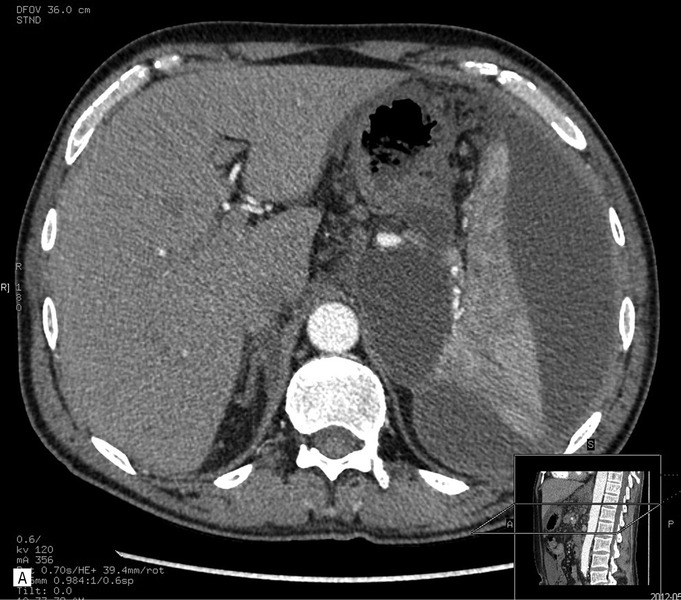

55-letni mężczyzna został przyjęty na oddział chirurgiczny z powodu silnych bólów brzucha, wymiotów i zaburzeń oddawania stolca – objawów sugerujących ostre zapalenie trzustki. W badaniach laboratoryjnych potwierdzono rozpoznanie. Wykonano badanie USG, które ujawniło powiększenie trzustki i zatarcie jej echostruktury. Pełną ocenę utrudniało napięcie powłok brzusznych, obrzęk krezki oraz obecność gazu w rozdętych pętlach jelit. Wykonano dwufazowe badanie TK, które potwierdziło obecność obrzękowej postaci zapalenia trzustki. Nie stwierdzono wówczas płynu w jamie otrzewnej. Śladowa ilość płynu była widoczna w lewej jamie opłucnowej (ryc. 1).

Rycina 1. Badanie TK w ostrej fazie zapalenia trzustki. A. Przekrój poprzeczny. Widoczne znaczne poszerzenie trzustki (obrzęk) z obecnością nacieku zapalnego w otaczającej tkance tłuszczowej, penetrującego wzdłuż naczyń w kierunku widocznej fragmentarycznie (biegun przedni) śledziony. B. Przekrój czołowy. Widoczna niepowiększona śledziona. Cechy nacieku zapalnego w okolicy przedniego bieguna. Bez cech nacieku i przestrzeni płynowych w otoczeniu nerek i mięśni biodrowo-lędźwiowych.